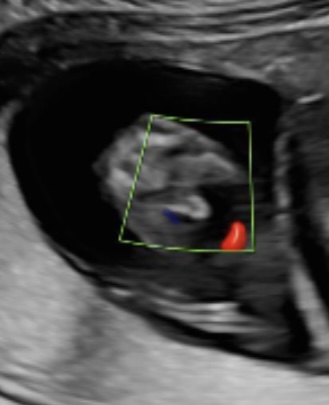

جنين في الاسبوع ١٤

ممكن اعرف نوع الجنين هل هو ذكر؟ ولا حبل السري